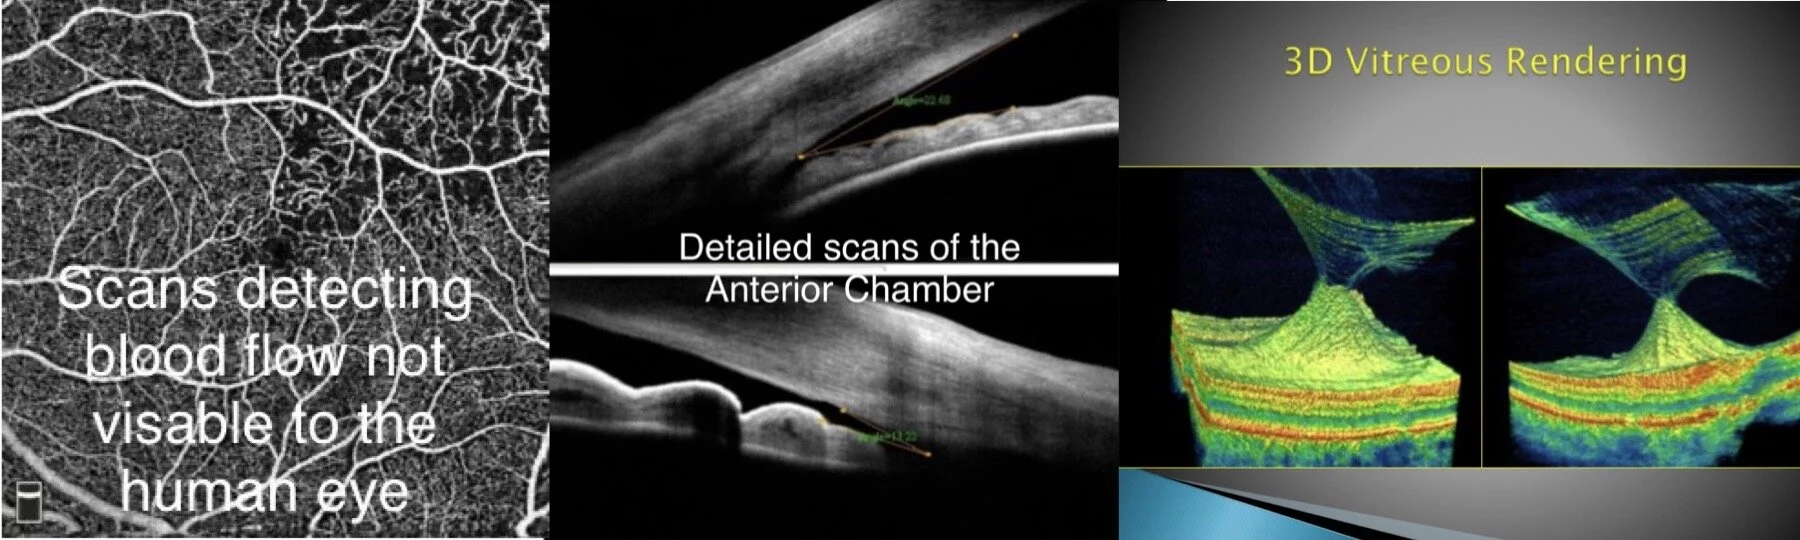

To provide the best patient care possible, we offer a host of in-house testing ranging from cutting-edge Optovue Avanti to Virtual Visual Field Testing to Pan-retinal imaging and dry disease testing including Infrared meibography.

With the complete offering of retina, optic disc, RNFL & GCC, and anterior segment scanning as standard, the Avanti is the perfect advanced, yet easy-to-use OCT for clinical practices. With the ability to screen and detect glaucoma up to five to ten years earlier than standard eye examinations is key in its successful management.